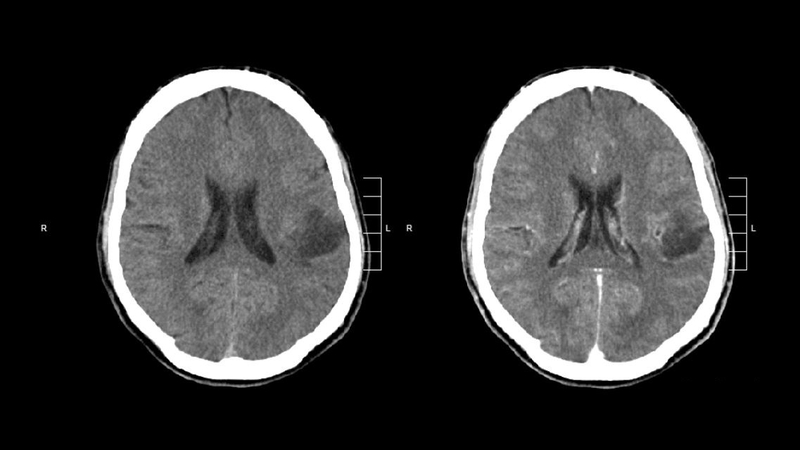

U thần kinh đệm ác tính (high-grade glioma), đặc biệt là glioblastoma, là dạng ung thư não ác tính phổ biến nhất ở người trưởng thành. Theo thống kê, các loại u thần kinh đệm chiếm khoảng 30 - 40% tổng số u não nguyên phát, trong đó glioblastoma chiếm khoảng 45 - 50% các trường hợp u thần kinh đệm.

Đặc điểm nguy hiểm của loại u này là khả năng xâm lấn lan tỏa dưới dạng “rễ nhện” vào mô não lành.

Khác với nhiều loại u đặc khác có thể bóc tách dễ dàng, tế bào ung thư trong u thần kinh đệm ác tính thâm nhập sâu vào tổ chức não, khiến việc phẫu thuật cắt bỏ hoàn toàn gần như là không thể.